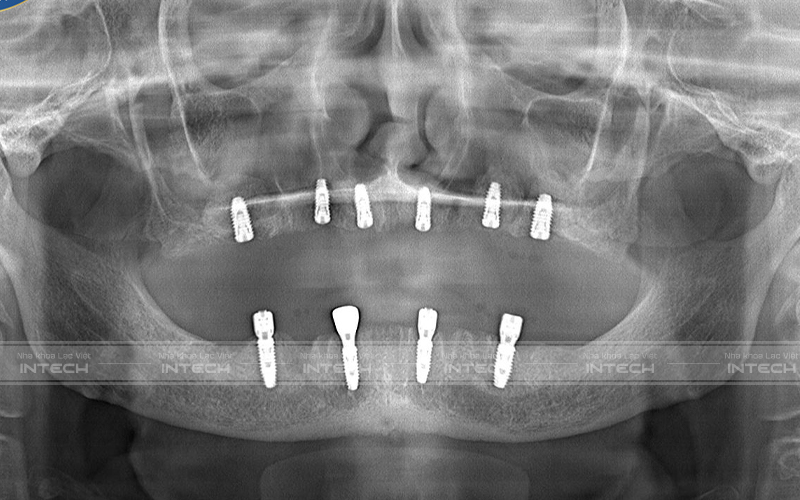

Dưới đây là hình ảnh phim chụp X-quang của chú Nguyễn Minh Sơn sau khi cấy ghép implant:

Hình ảnh phim chụp sau cấy ghép implant của chú Nguyễn Minh Sơn - Trụ implant được đặt ở những vị trí chính xác (Ảnh: Nha khoa Lạc Việt Intech)